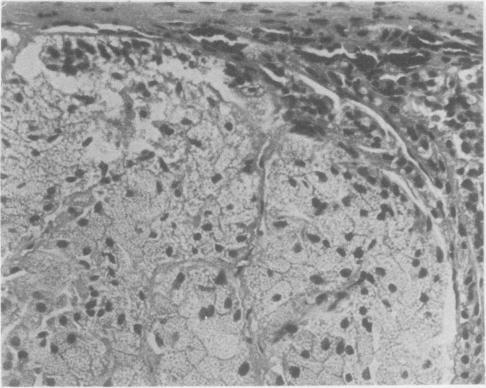

A case of primary tumorous aldosteronism due to a black adrenal adenoma in a 37-year-old man is reported. Light microscopy showed the tumour to consist predominantly of compact cells containing intracytoplasmic lipofuscin, accompanied by zona fasciculata and intermediate type cells. Electron microscopy identified compact and interface (inner zona fasciculata) type cells, and also demonstrated spironolactone bodies in a compact cell. The morphological appearance of the tumour and adjacent adrenal gland, combined with the clinical and biochemical findings, supports both its secretory function and its classification as a rare variant of the more common non-pigmented aldosteronoma.

报告了一例37岁男性因黑色肾上腺腺瘤导致的原发性肿瘤性醛固酮增多症。光镜检查显示肿瘤主要由含有胞浆内脂褐素的致密细胞组成,并伴有束状带和中间型细胞。电镜鉴定出致密型和界面(束状带内层)型细胞,并且在致密细胞中发现了螺内酯小体。肿瘤及相邻肾上腺的形态学表现,结合临床和生化检查结果,支持其分泌功能以及将其分类为更常见的非色素性醛固酮瘤的一种罕见变体。